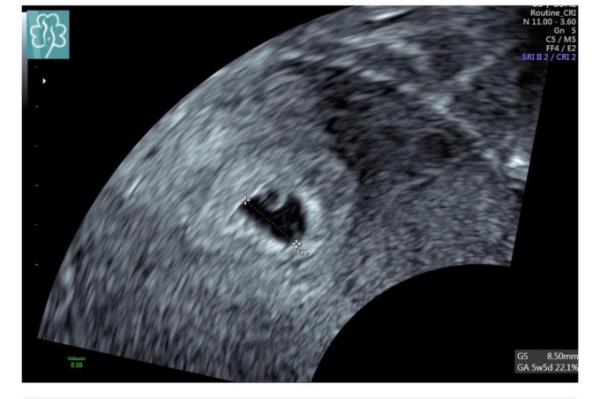

Antwort auf Beitrag von Jasmin9827

Und 8+0... Wurde zurückdatiert auf 6+4